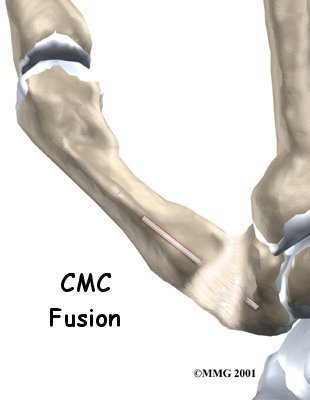

Thumb Fusion Surgery

Thumb arthritis may be surgically treated with a fusion procedure. The bones that form the thumb joint are set so they can grow together, or fuse. A fusion keeps the problem joint from moving so that pain is eliminated.